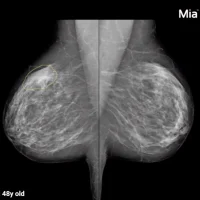

Saving lives is the most important thing any physician can do. Radiologists are in a position to not only save lives, but with the right tools, like the Hologic Genius™ 3D Mammography™ exam, they can detect cancer earlier, when it’s most treatable. Did you know that in clinical studies, our 3D™ exam:

• Delivers a series of detailed breast images, allowing radiologists to better evaluate their patients’ breasts layer by layer.1

• Has greater accuracy than 2D mammography for women across a variety of ages and breast densities.2-7

• Is the only mammogram FDA approved as superior for women with dense breasts.1,2*